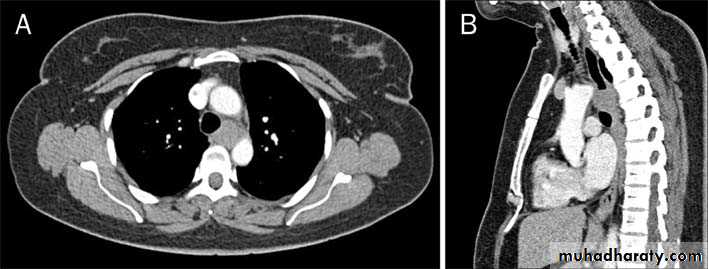

CausesEsophageal atresia

Types:• isolated atresia 8%

• Proximal fistula with distal atresia 1%

• Proximal atresia with distal fistula 85%

• Double fistula with intervening atresia 1%

• Isolated fistula [H-type] 4%